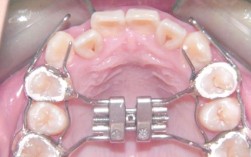

在技术设备方面,珠海摩尔口腔正畸引入了全套数字化正畸系统,包括3D口内扫描仪、CBCT影像设备、AI方案设计软件等,可实现牙齿数据的精准采集与三维重建,通过数字化模拟,医生可在术前直观展示矫正后的牙齿排列效果与面部形态变化,让患者提前预见矫正成果,机构与国际知名矫治器品牌深度合作,提供传统金属托槽、陶瓷半隐形托槽、隐形矫治器(如时代天使、隐适美等多种品牌)及自锁托槽等多种矫治方式,满足不同患者的美观需求、舒适度要求及预算范围。

服务流程上,珠海摩尔口腔正畸遵循“个性化评估-方案定制-精准矫治-长期维护”的标准化路径,初诊阶段,医生会通过口腔检查、X光片拍摄、模型取模等全面评估患者的牙齿状况、骨骼发育及牙周健康;方案设计阶段,结合患者年龄、主诉及面部美学特征,利用数字化工具模拟牙齿移动路径,制定包含矫治周期、注意事项及预期效果的详细方案;矫治过程中,医生定期跟踪牙齿移动情况,及时调整矫治力,确保矫正进度与计划一致;矫正结束后,为患者提供个性化保持器及长期的口腔健康维护指导,有效防止复发。